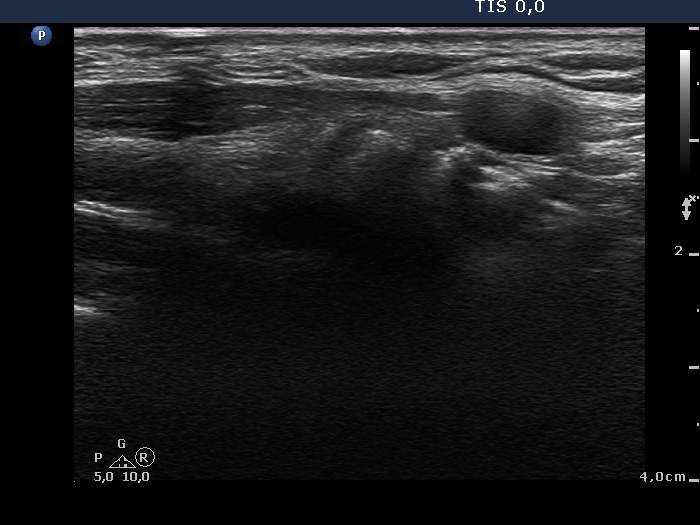

Ultrasound. Connective tissue replaced the thyroid parenchyma in both thyroid beds. There were tiny hypoechoic areas in the right thyroid bed. Two larger hypoechoic lesions were found, one in the isthmus and the other in the left thyroid bed. The latter presented vascularity.

Comment. The presentations of the hypoechoic lesion in all three sites were the same, they differed only in their size. Naturally, the two larger in the isthmus and in the left thyroid bed could cause and did cause concern. Especially that in the left lobe due to its intralesional vascularity. The larger lesions can correspond to small muscle fibers, remnant of the regenerative provess after the surgery but even damaged, non-viable thyroid tissue. Taking the thyroglobulin level into account, the risk of thyroid cancer is minimal but not zero.